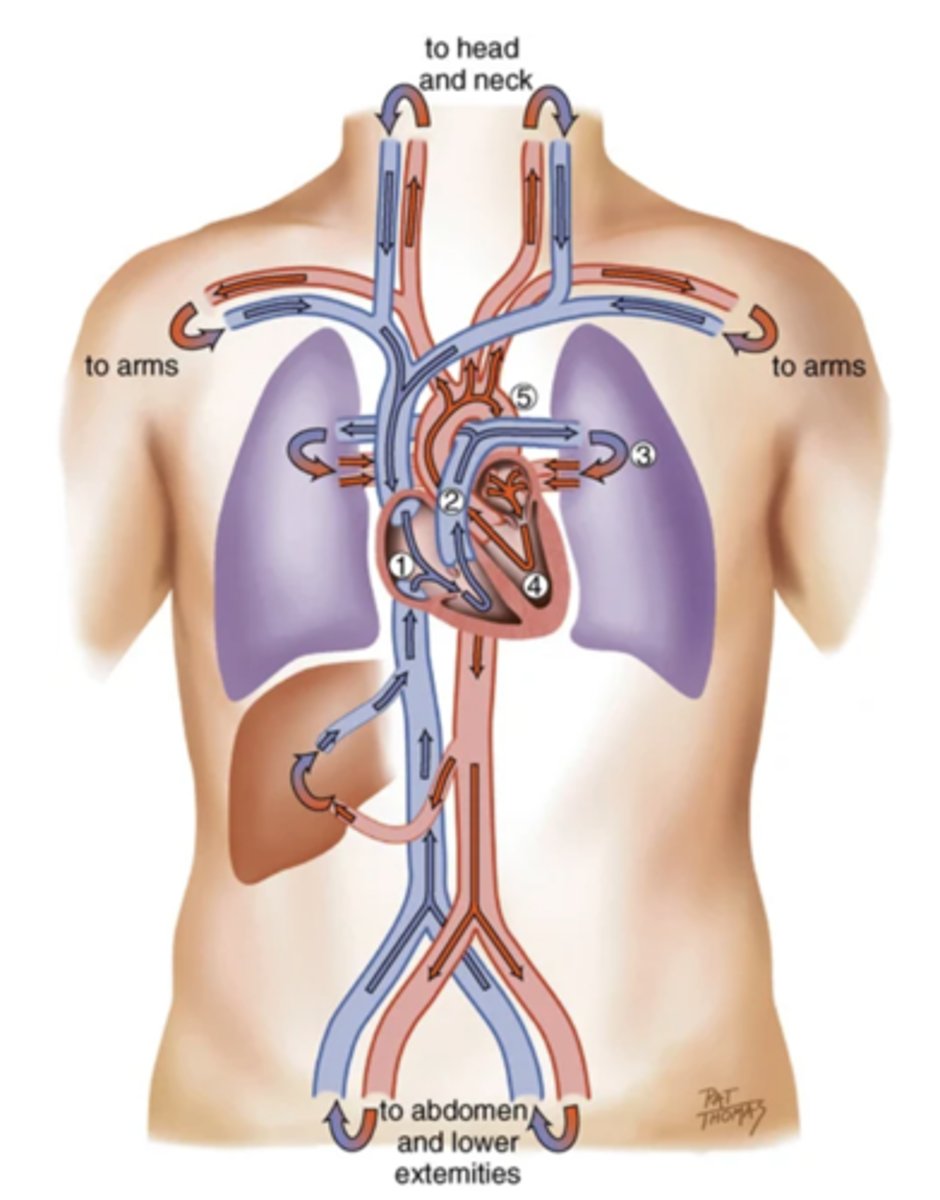

Blood Flow

Cardiac Cycle

A complete heartbeat consisting of contraction and relaxation of both atria and both ventricles

2 Phases of the Cardiac Cycle

- Diastole

- Systole

Diastole

The phase of the cardiac cycle where the ventricles relax and fill with blood (relaxation)

Systole

The phase of the cardiac cycle where blood is pumped from the ventricles and fills the pulmonary and systemic arteries (contraction)

The 4 Great Vessels of the Heart

- Superior/inferior venae cavae

- Pulmonary artery

- Pulmonary veins

- Aorta

Superior/Inferior Venae Cavae

The large veins that empty into the right atrium of the heart and return unoxygenated venous blood to the right side of the heart

Pulmonary Artery

Artery carrying oxygen-poor blood from the heart to the lungs

Pulmonary Veins

Veins carrying oxygenated blood from the lungs to the heart

Aorta

The largest artery in the body which carries oxygenated blood from the heart throughout the body